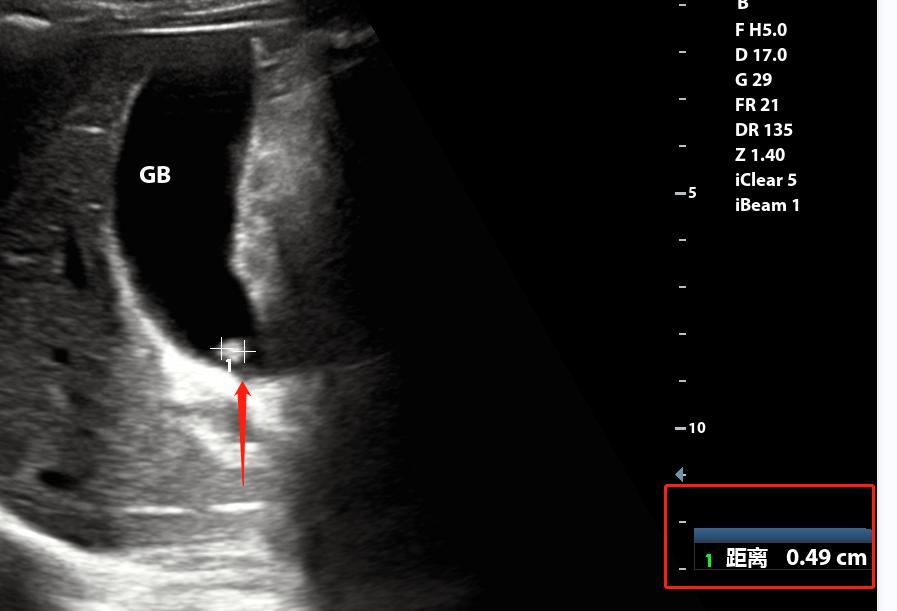

仔细一想“胆囊结石是随体位移动,要不在床上打两个滚?”

“李四啊,你这样,在床上滚两下,对,就是这样左边翻一下,右边翻一下。。”

好歹李四年龄不大,50多岁,翻滚四五个来回后,又从肋间瞅瞅。

终于滚出来了

此时我明确地告诉李四“你确实有结石”,李四也回应了“哦”,估计心想“我早就知道了”